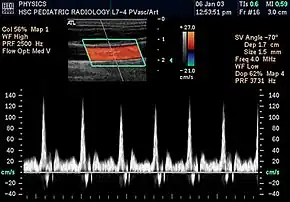

![]() Spectral duplex scan of the common carotid artery | |

Doppler ultrasonography is medical ultrasonography that employs the Doppler effect to perform imaging of the movement of tissues and body fluids (usually blood),[1][2] and their relative velocity to the probe. By calculating the frequency shift of a particular sample volume, for example, flow in an artery or a jet of blood flow over a heart valve, its speed and direction can be determined and visualized.

Duplex ultrasonography sometimes refers to Doppler ultrasonography or spectral Doppler ultrasonography.[3] Doppler ultrasonography consists of two components: brightness mode (B-mode) showing anatomy of the organs, and Doppler mode (showing blood flow) superimposed on the B-mode. Meanwhile, spectral Doppler ultrasonography consists of three components: B-mode, Doppler mode, and spectral waveform displayed at the lower half of the image. Therefore, "duplex ultrasonography" is a misnomer for spectral Doppler ultrasonography, and more exact name should be "triplex ultrasonography".[3]

Colour Doppler shows the direction of the blood flow in red or blue (either towards or away from the transducer). Meanwhile, spectral Doppler not only shows the direction of blood flow, it also shows the phases (pulsatility) and acceleration of the blood flow. Any sudden changes in direction of blood flow produces audible sounds on the ultrasound machine.[3]

In spectral Doppler, the y-axis shows the direction and velocity of the flow. Meanwhile, the x-axis (as known as "baseline") shows the flow over time. The gradient at any point on the waveform would therefore shows the acceleration of the flow. In "antegrade" flow, the blood flows according to the normal flow within the circulatory system (e.g. veins flow towards the heart while arteries flows away from the heart). In "retrograde" flow, the flow would reverse (e.g. veins flow away from heart or arteries flow towards the heart). However, "retrograde" flow can be both abnormal or normal. For example, in portal hypertension, there is an abnormal portal venous flow where it flows away from the liver (hepatofugal flow) instead of the normal flow towards liver (hepatopetal flow). In jugular venous pressure waveform of the internal jugular vein, the retrograde "a" waveform is a normal flow due to right atrium contraction. Both antegrade or retrograde flow can be either towards or away from the probe transducer, depending on the position of the probe relative to the blood flow. Blood flow toward the transducer would appear above the baseline while blood flows away from the transducer will appear below the baseline. Waveform of the flow can be classified as: pulsatile (as in arteries), phasic (as in veins), non-phasic (as in diseased veins), and aphasic (no flow). Spectral broadening (thickness of the waveform) increases from large vessels (plug flow) to medium vessels (laminar flow) to small/stenotic/diseased vessels (turbulent flow) due to a larger variety of blood with different ranges of velocities in those with turbulent flow.[3]